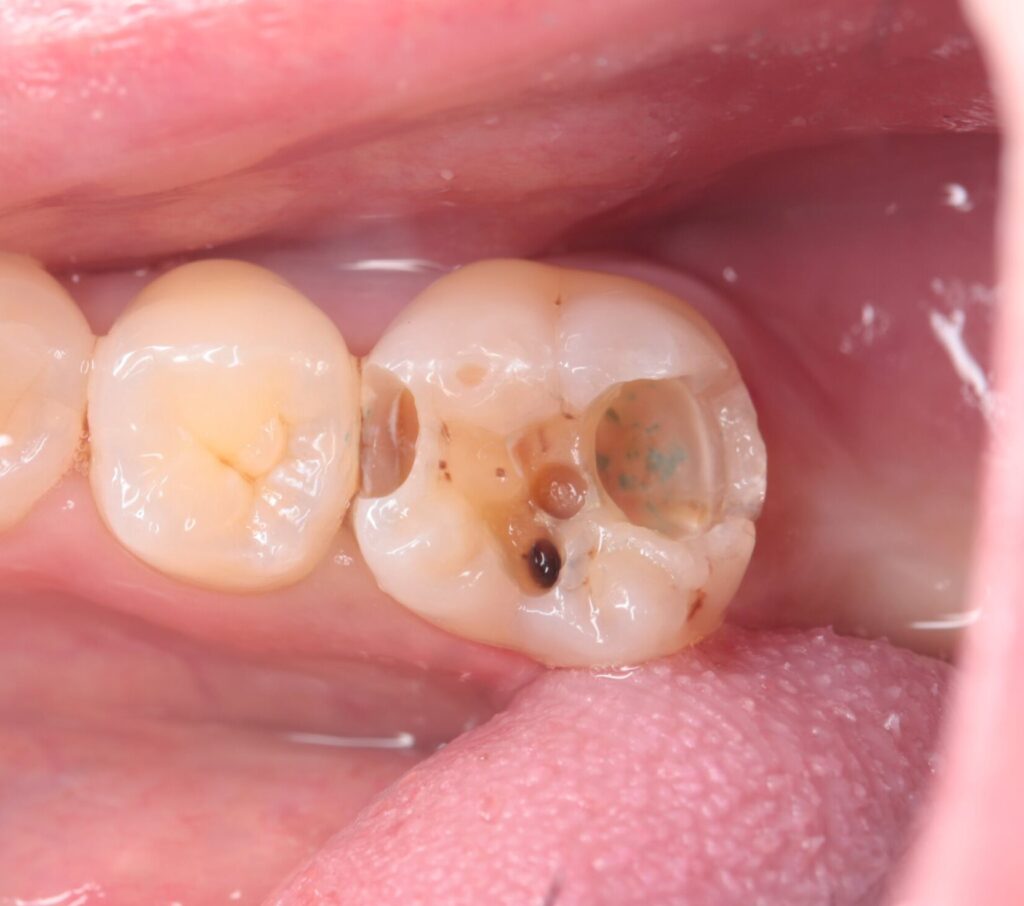

歯が大きく失われたむし歯

歯が大きく欠け、噛みにくくなる段階です。強い痛みが出ることもありますが、痛みが特にない場合もあるため注意が必要です。